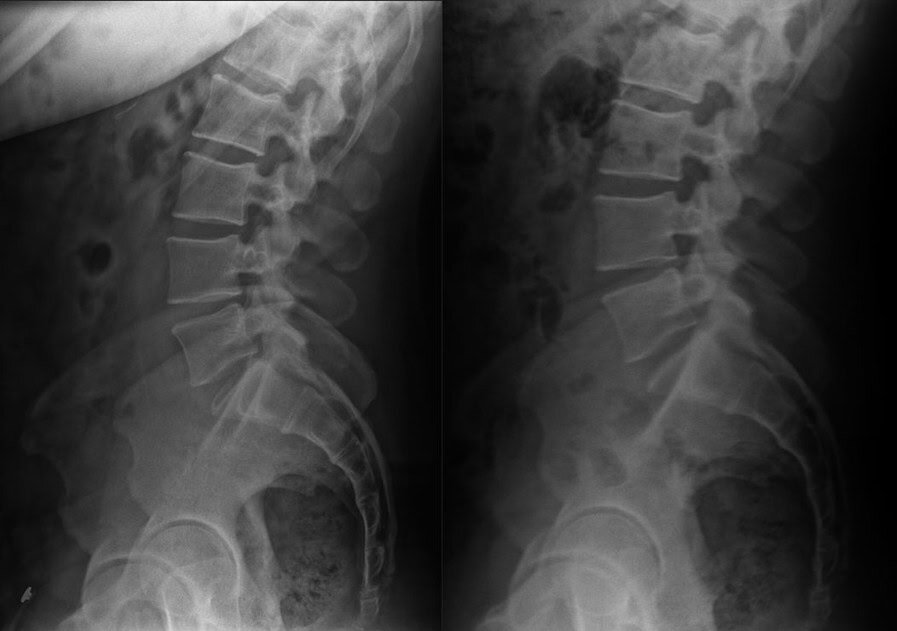

Pre & Post Scan